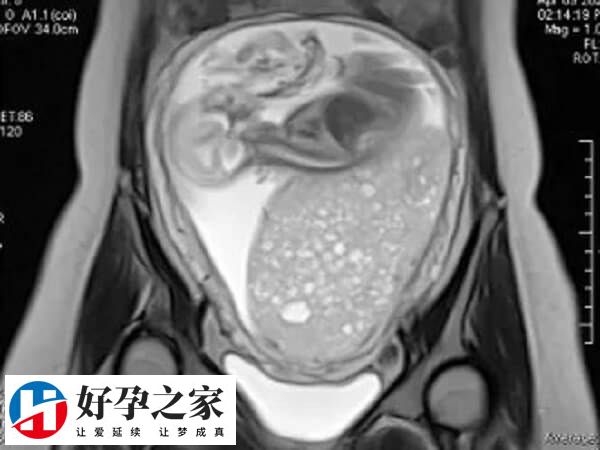

“卵巢”的功能是产生“卵子”。卵子与卵泡中的卵泡同步成熟。发育良好的卵子是试管婴儿成功的保证。然而,这些卵太小,肉眼看不见。为了在试管婴儿中成功获得优质卵子并将其制成胚胎,卵子的发育只能通过观察卵泡间接推断。在卵泡发育过程中,一种更简单直观的评估方法是通过超声进行观察。通过每个周期3-4次的超声监测,我们可以观察是否有正常的卵泡生长、发育,以及何时可以进行取卵手术。

在试管婴儿超排过程中,卵泡监测是为了评估卵巢刺激的效果,并确定取卵的时间。当两个以上的卵泡直径大于18mm时,“夜针”可以在当天注射人绒毛膜促性腺激素(HCG),以促进卵泡的成熟。注射HCG后36小时收集卵。